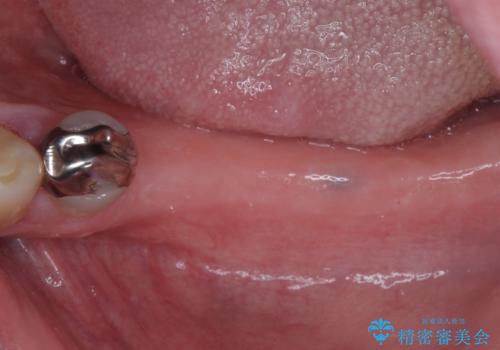

欠損の多い奥歯 インプラントによる補綴治療

上顎は左右ともに骨が少ない状態であり、特殊なドリルを用いた歯槽骨の拡大や自家骨挙上などを行いながらインプラントを埋入していくこととしました。